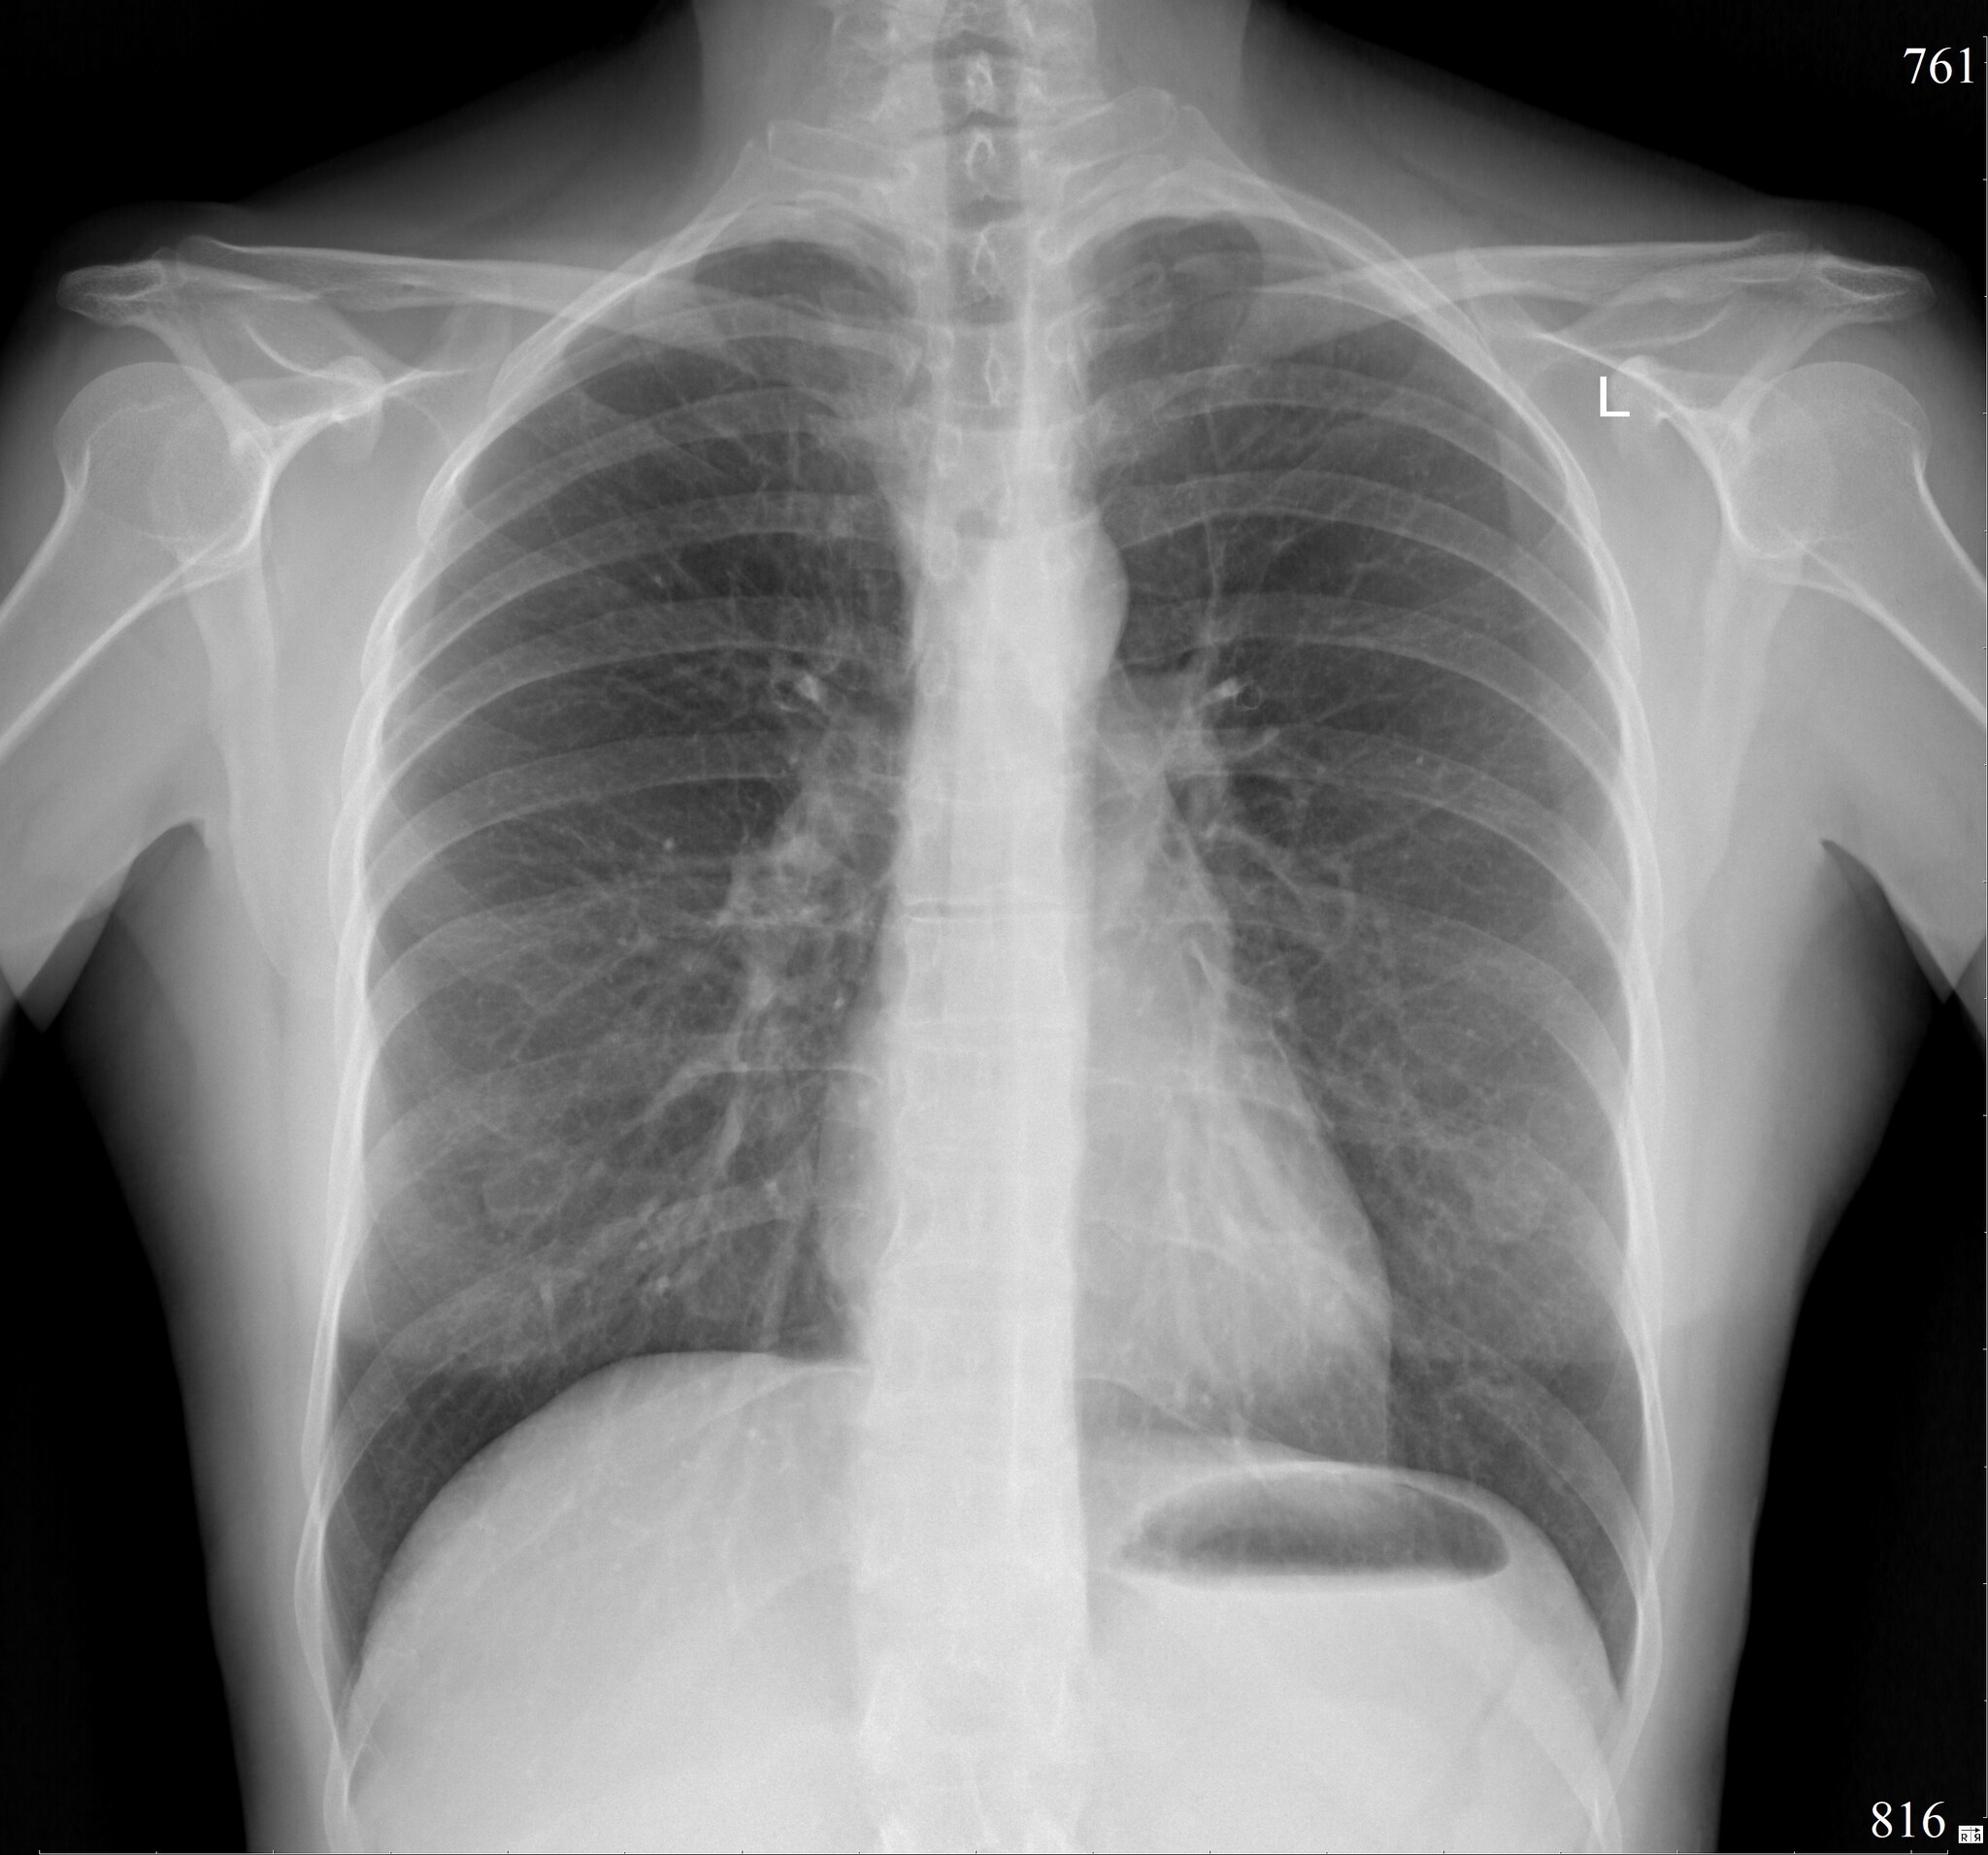

Итак, позвольте представить - situs inversus.

Это состояние, при котором в теле человека все внутренние органы грудной клетки и живота зеркально отражены - сердце справа, желудок и селезёнка справа, печень слева, также отзеркалены сосуды, нервы, кишечник (в том числе аппендикс).

Ну и бонусом - как выглядят "нормальные" лёгкие.